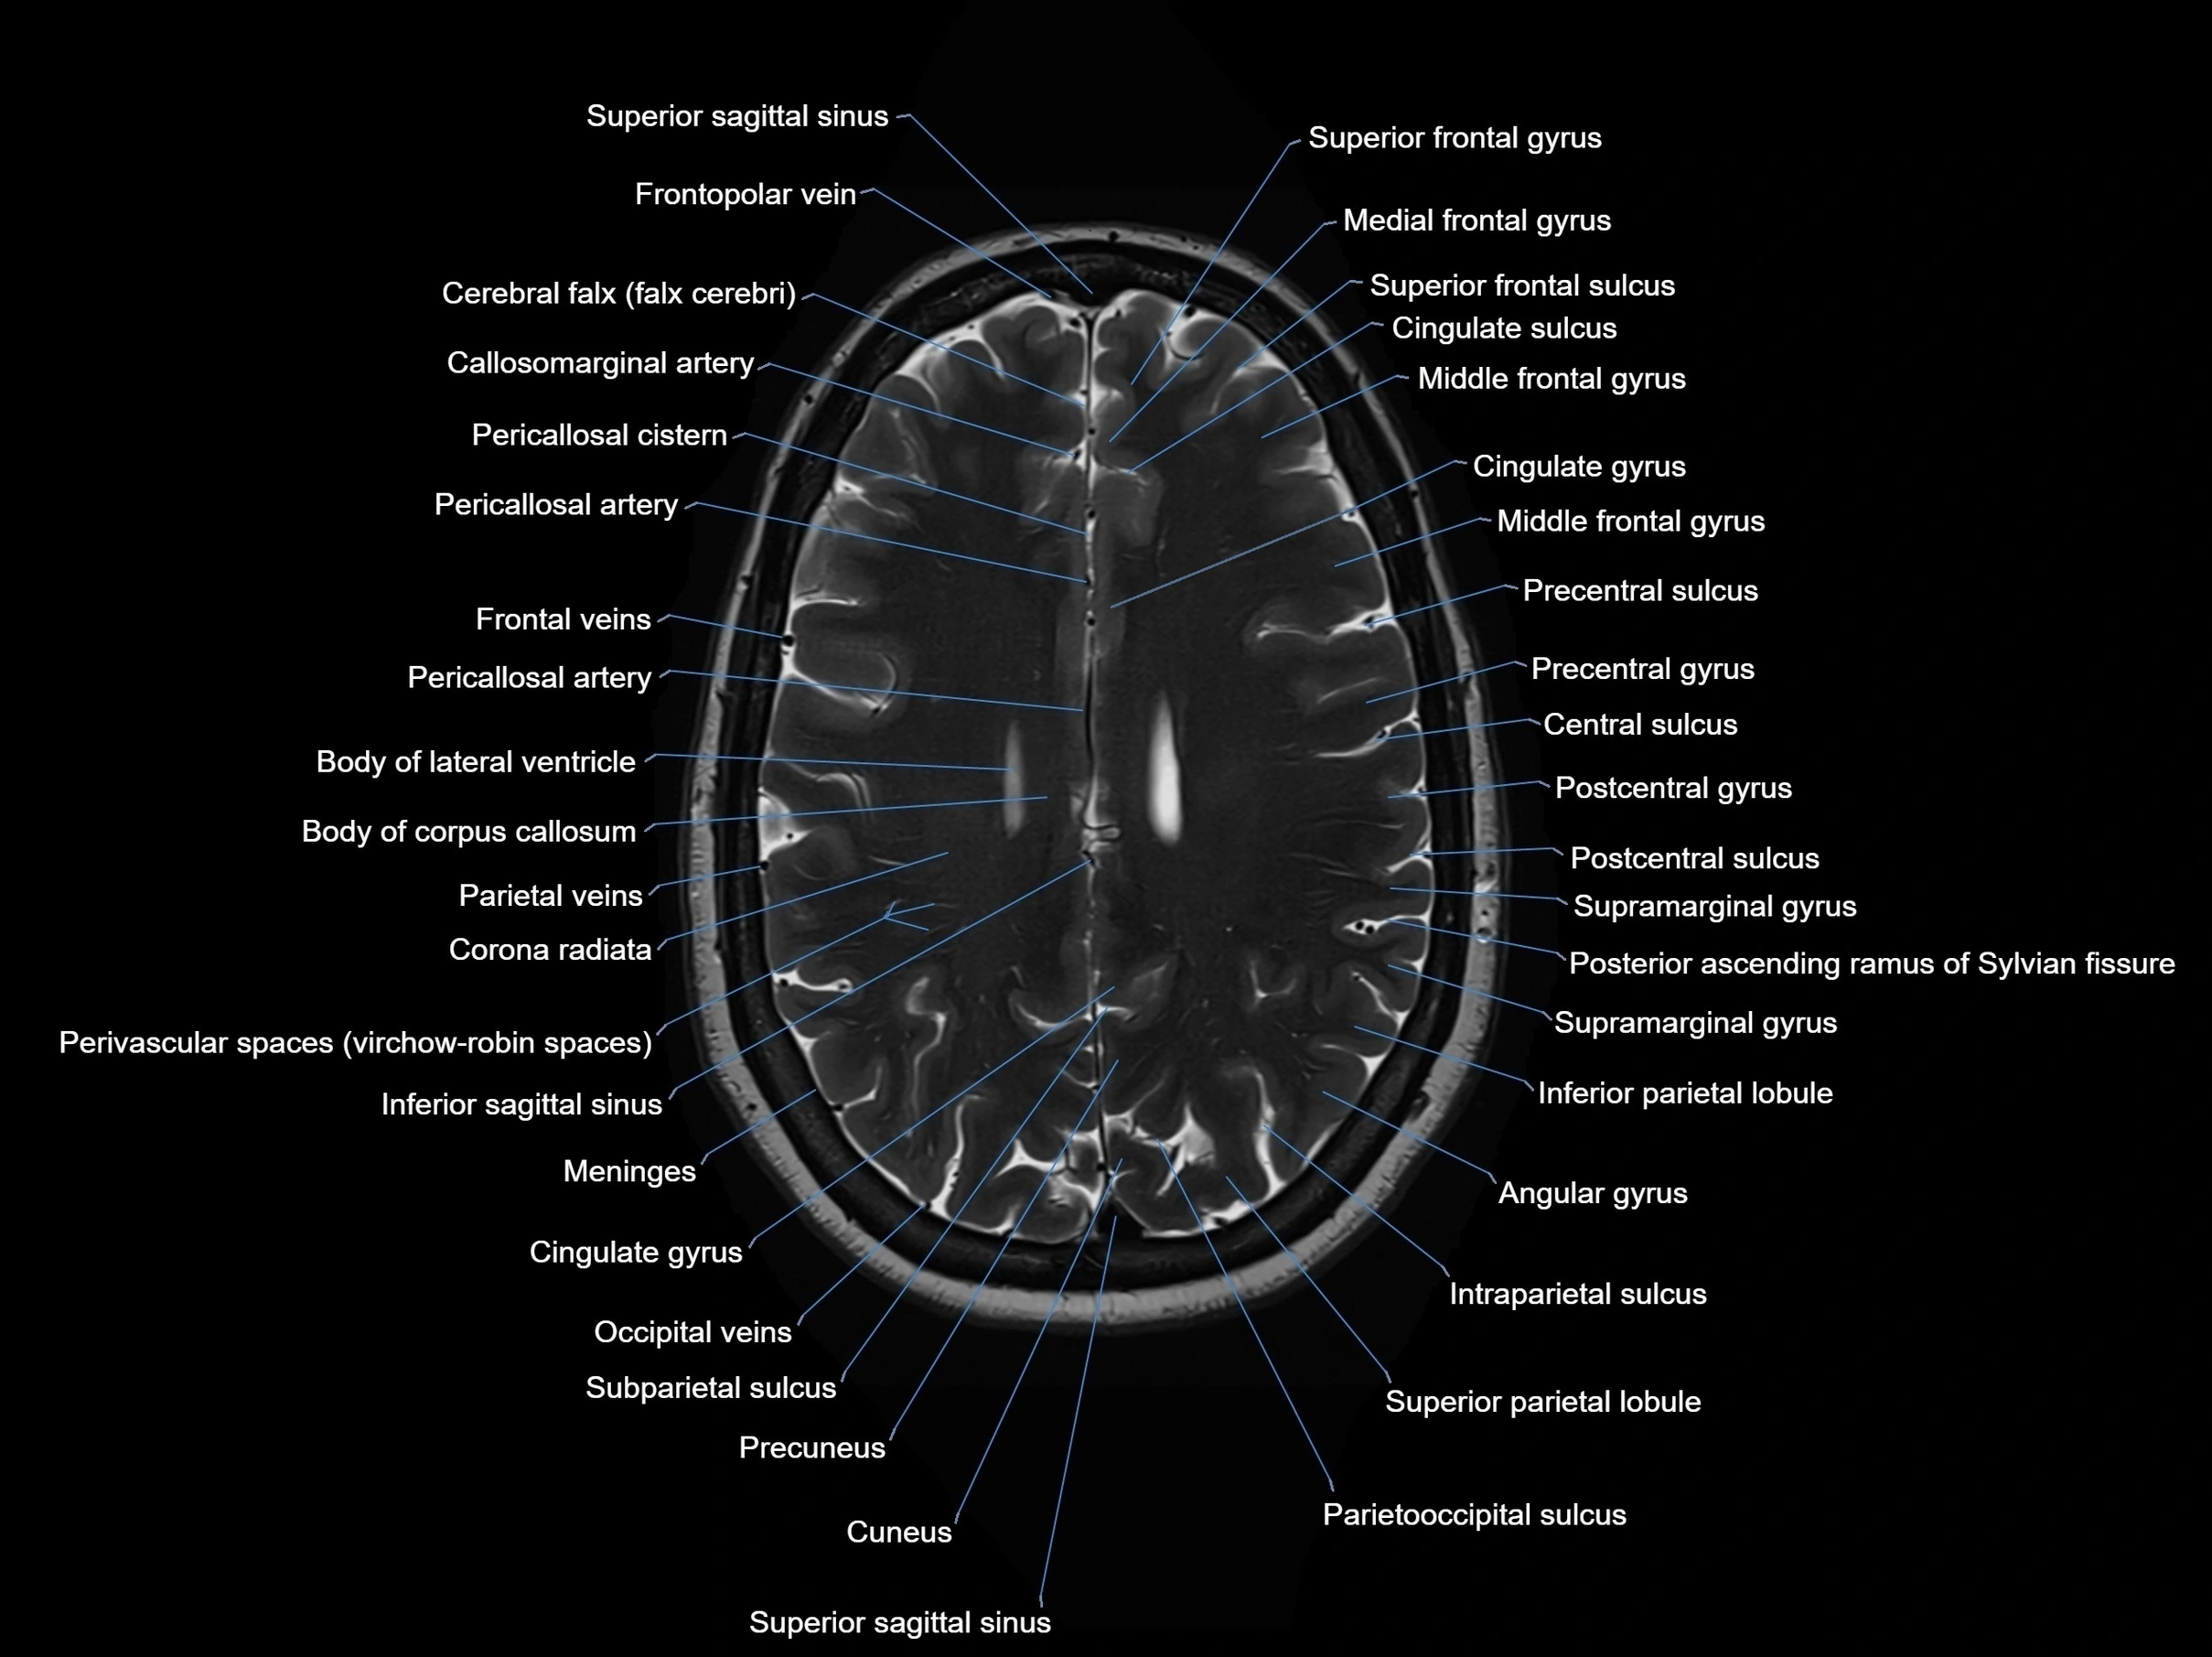

MRI images